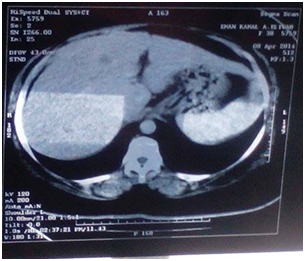

Thirty-three patients of MTNBC presented in a period from February 2013 to March 2015 were treated with gemcitabine\carboplatin. Patients had a median age of 43.6years (range, 24-71 years, S.D: 11.161)23 patients were premenopausal (69.7%) & 10 patients were postmenopausal (30.3%). Approximately 81% of patients had a good PS (0-1). 12 patients were basal subtype (positive ck5/6) from twenty patients who had accessible specimens for examination of cytokeratin (12out of 20=60%), Mean overall survival (OS) in patients has basal subtype were 12 months, while in patients has non-basal subtype were 12.96 months (95% CI-3.53-5.45) P <0.242). Median progression-free survival (PFS) in basal subtype were 5.857 months while in non-basal subtype were 6.15 months (95% CI-1.79738-2.39079) P <0.456).patient had complete response (CR) Figure 1.

Figure 1 Liver metastasis, a. Before treatment & b. After treatment.